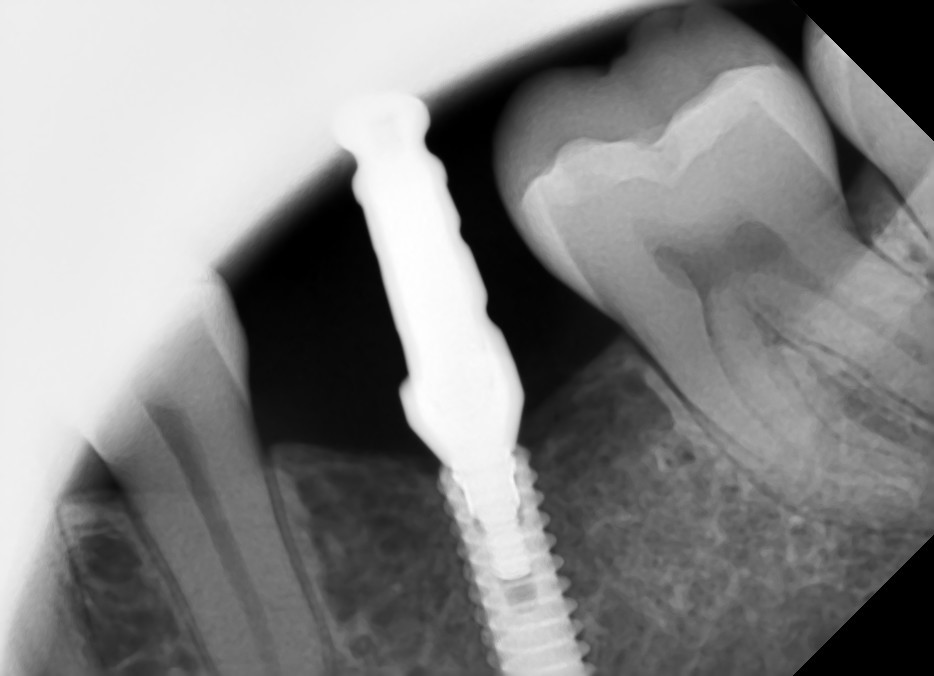

Follow-up panoramic radiograph following the installation of the implant with the gingiva former. The measurements of the implant: diameter: 3.3 mm, length: 13 mm, DIO implant.

Follow-up panoramic radiograph with the finished screw-retained implant crown.